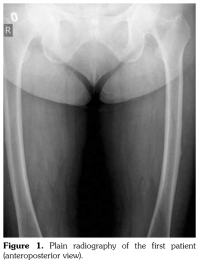

Case 2– A 61-year-old female patient presented with anterior thigh pain and difficulty in walking. Pain severity was 7 over 10 point according to visual analog scale. She had been treated with alendronate 70 mg per week with calcium plus vitamin D for two years. Plain radiographs of femur were taken upon clinical presentation. Cortical stress reaction was detected in both femoral shafts on plain radiographs (Figure 2). Computed tomographic imaging was performed to rule out fracture (Figure 3). Bone scintigraphy showed increased uptake in distal (1)/3 ends of femoral shafts (Figure 4). Serum calcium value was normal and urinary deoxypiridinoline level was mildly increased (46 nM/mMCre).

At the time of diagnosis, dual-energy X-ray absorptiometry results were as follows: femur neck total bone mineral density was 0.782 g/cm(2) and T score was -1.8; L2-L4 bone mineral density was 0.865 g/cm(2) and T score was -2.8.

After the diagnosis, we informed the patient about the cortical stress reaction. We advised her to restrict activities for two months and to use crutches during walking. Calcium and vitamin D supplements were prescribed along with strontium ranelate therapy. It has been one year since the diagnosis and her pain severity lessened and no fracture has been reported.